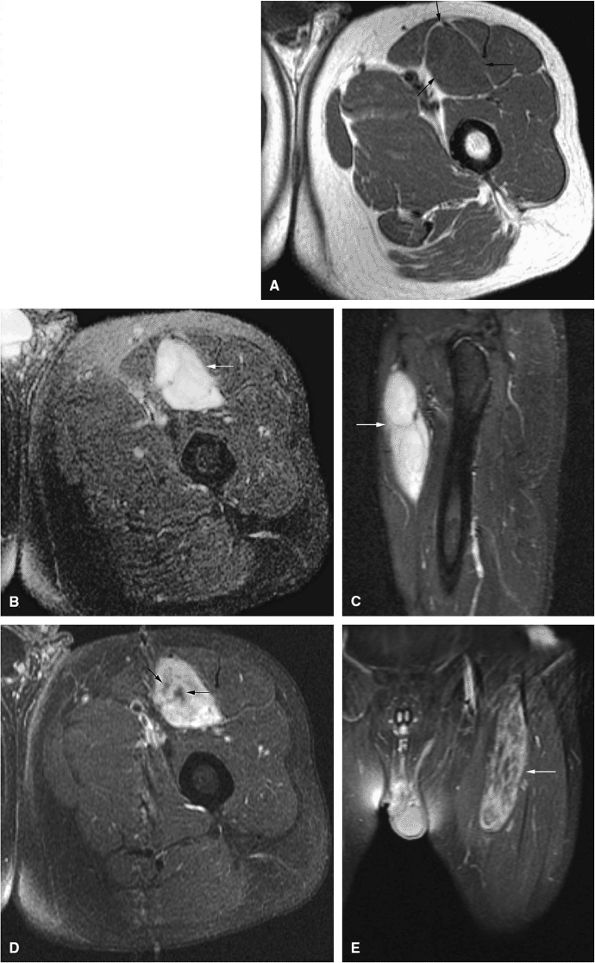

FIGURE 14-14 ● Cortical osteoblastoma of the femoral diaphysis. Coronal (A) and axial (B) T1-weighted images show osteoblastoma isointense to muscle with adjacent cortical thickening (arrows). Reactive bone marrow edema is hyperintense on sagittal (C) and axial (D) fat-suppressed T2-weighted fast spin-echo images (arrowheads).

Signal intensity may be heterogeneous or homogeneous on T2-weighted images (Fig. 14-14).

A diffuse inflammatory response involving bone and adjacent soft tissue has been reported in a case of vertebral osteoblastoma.54 CT may be more accurate for the identification of small foci of matrix calcification (Fig. 14-16).